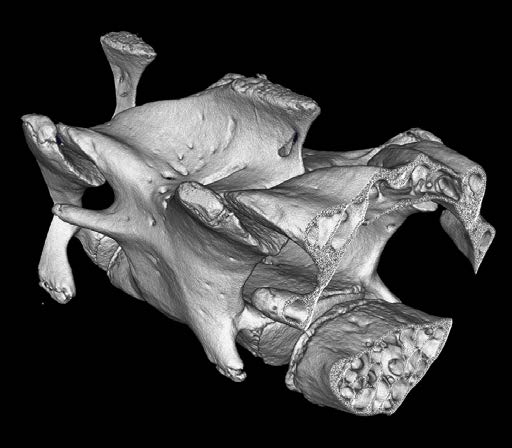

CosmoScan GX IIIは特に高い空間分解能を持ち、5µmまでの解像度と2.9µmのピクセルサイズ(FOV:8mm)を誇ります。これにより小さい骨の細かな解剖学的構造を含むex vivoサンプルの高品質な画像が得られます。

- 空間分解能 = 5µm 最小ピクセルサイズ = 2.9µm